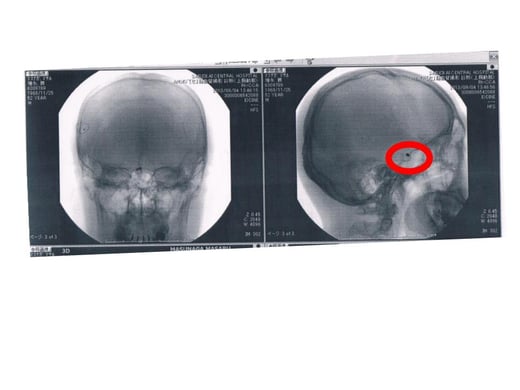

2012年9月25日脳血管内動脈瘤破裂によるくも膜下出血患部

私は、普段の不摂生が原因か、その数日間の寝不足が原因か、それとも全く与り知らない理由なのかはさて置き、2012年9月25日渋谷の居酒屋で脳内血管動脈瘤破裂によるくも膜下出血により倒れ、救急搬送されました。

私の患部は、左眼眼窩のすぐ奥(つまりは最深部)で、外科的な手術では、術野を確保するのが困難で匙を一度投げられたそうです。

名医は私の鼠蹊部から一直線に左眼眼窩奥の患部にカテーテルを挿入し、プラチナコイルを破裂した動脈瘤の内側にきっちり巻き上げて完璧に止血しました。

5時間の大手術。